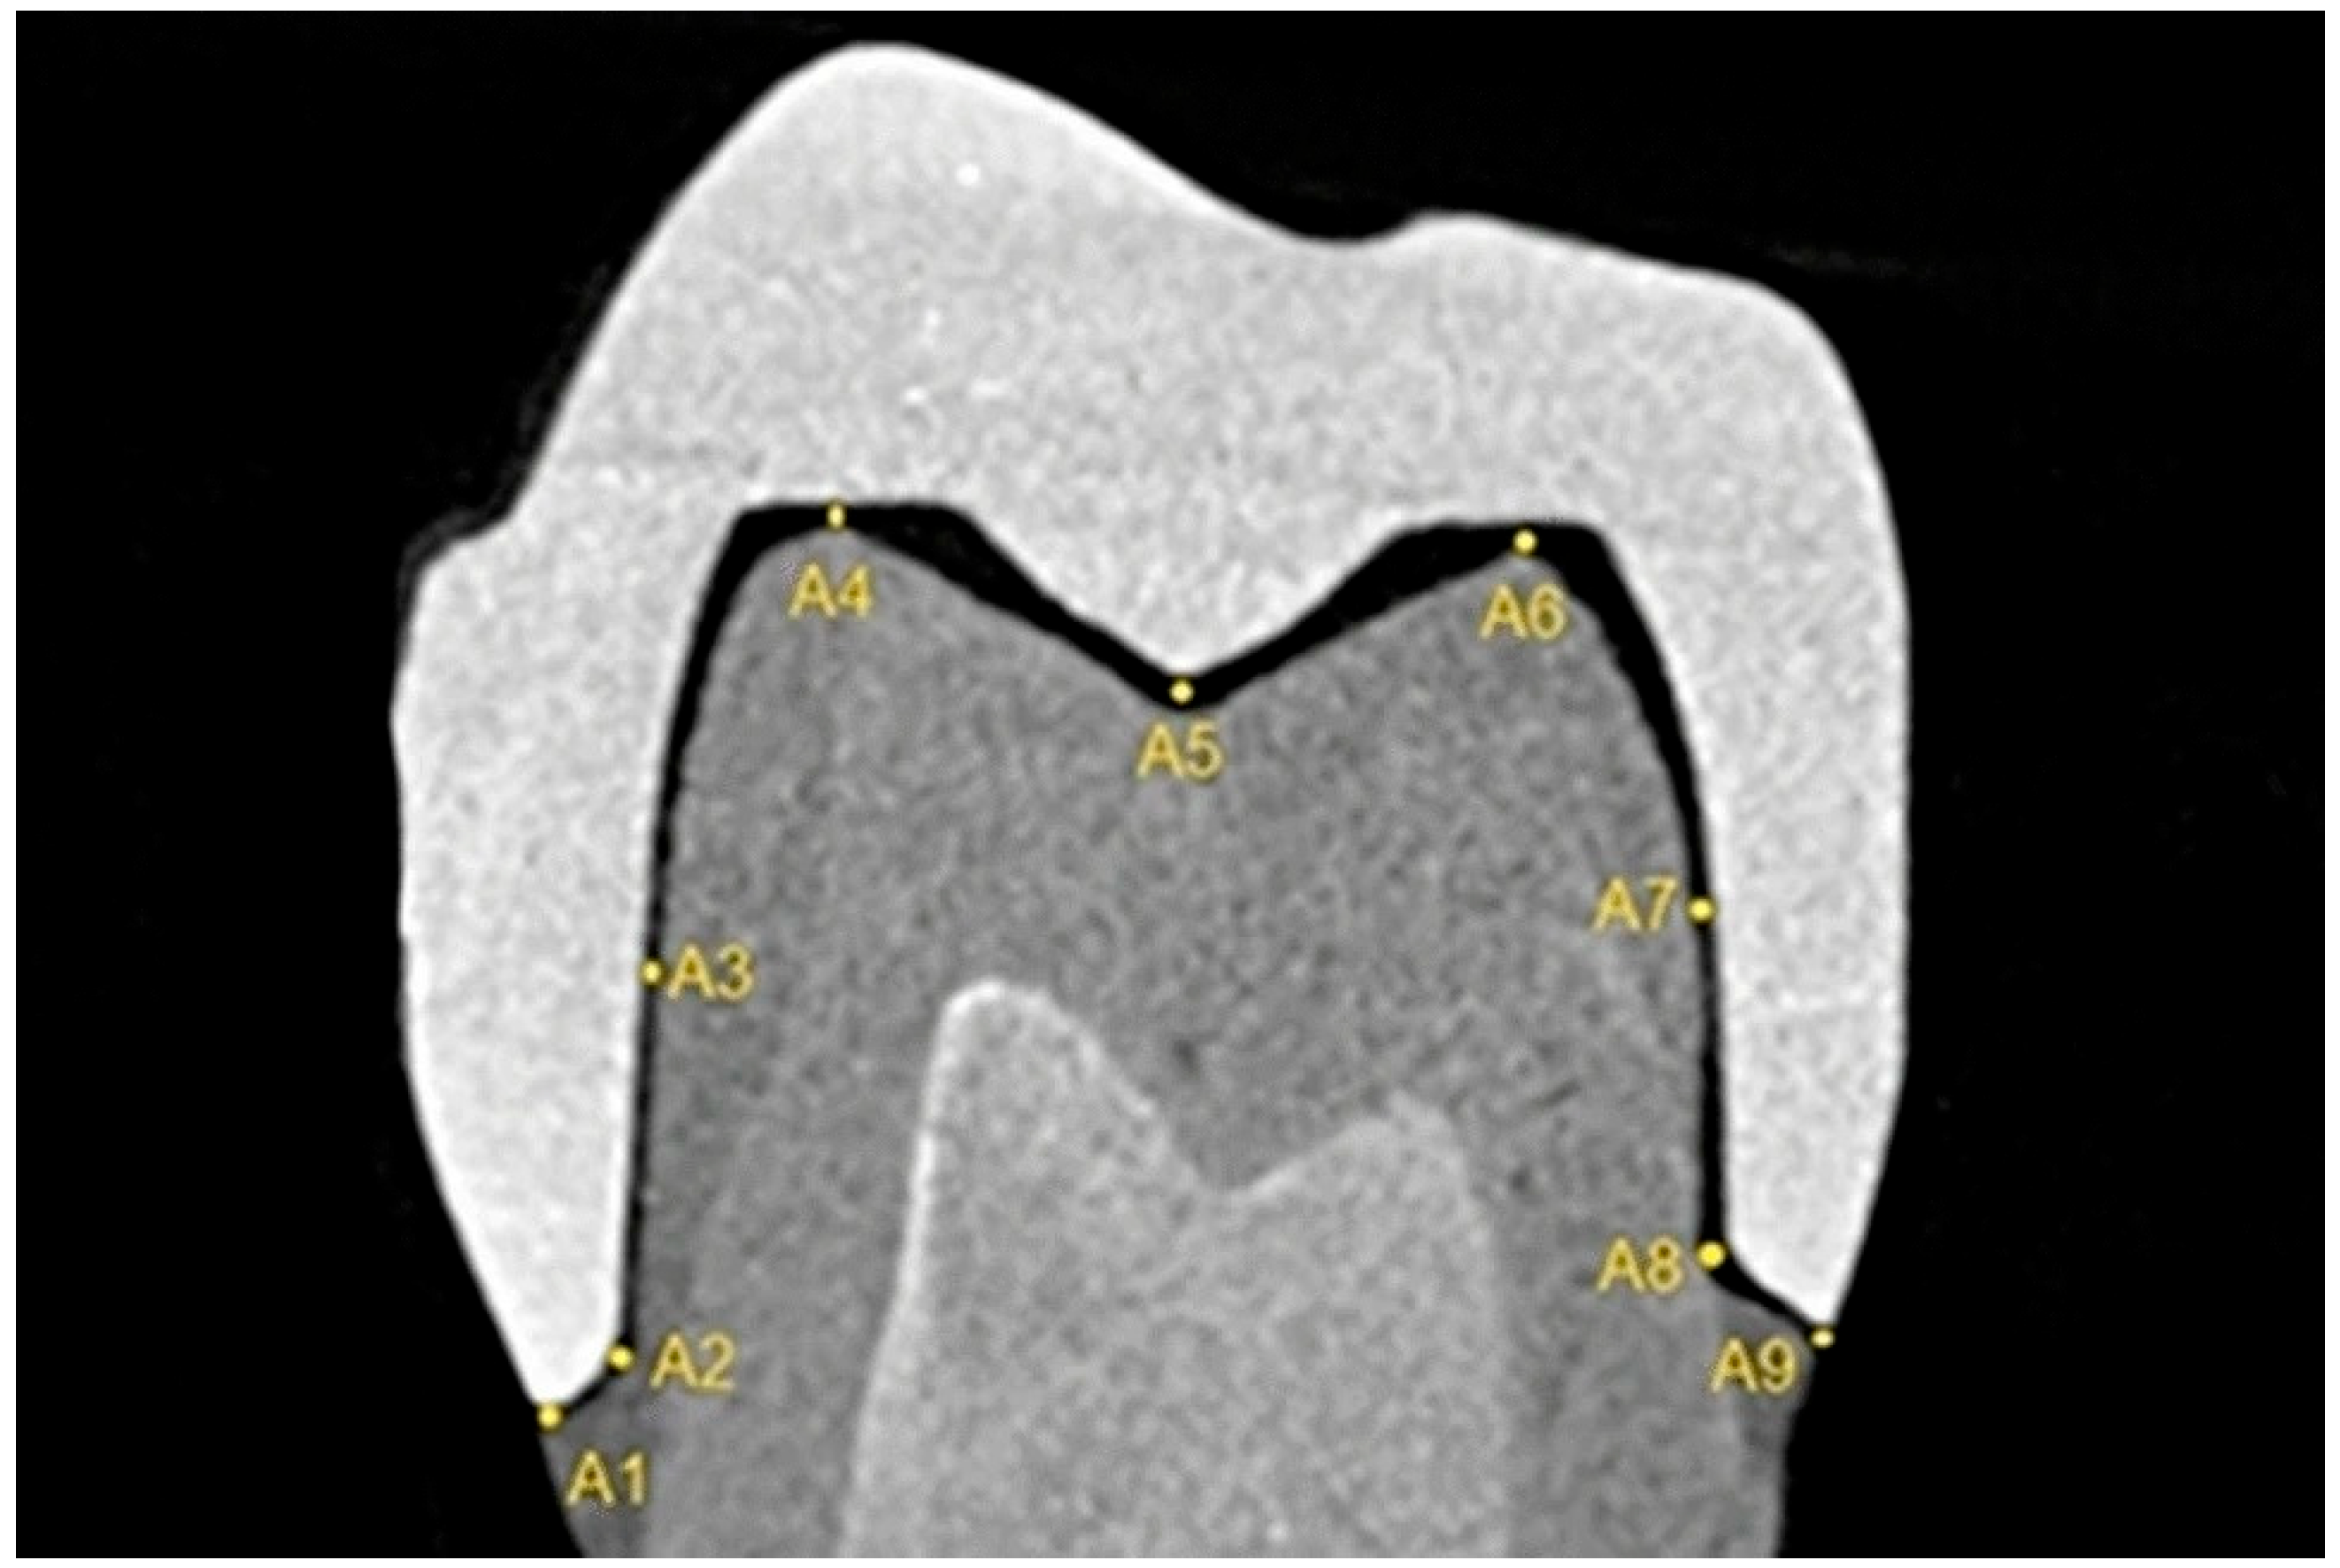

2.1. Linear Measurements